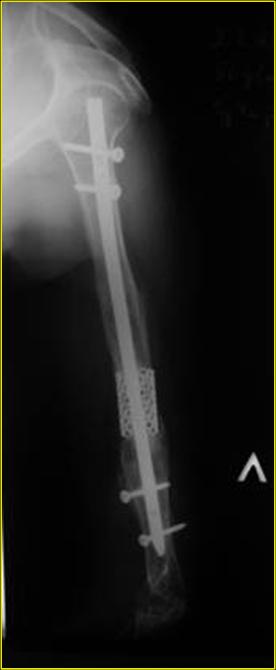

Рентгеновская версия реконструкции хронология в обратном порядке: 1,2

- через 1 год, 3,4 - 2 мес. после операции, 5,6 - после операции.

Движения в полном объеме востановлены к 2 мес. после операции. Если

надо могу  показать мультик. Сейчас уже прошло более 3 лет, больная не

показывается. Успехов ЛАФ.